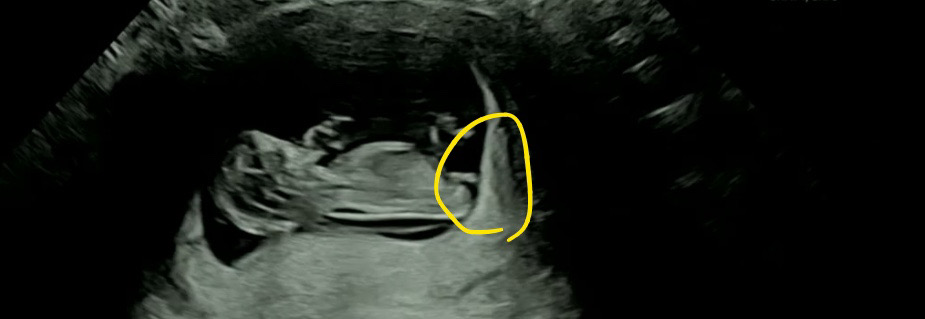

의사선생님이 꼬집어서 일자죠~?? 라고 하시더라구요 !? 투표좀 해주세요 ^^